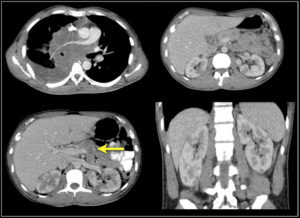

- Злокачественные солидные опухоли (саркомы, карциномы, глиомы) состоят из низко или умеренно дифференцированных клеток. Они быстро увеличиваются в размерах, прорастают окружающие ткани, разрушая их, а также могут давать метастазы (очаги отсеивания, расположенные вдали от первичного новообразования) и оказывают системное воздействие на организм. Они опасны для здоровья и несут смертельную угрозу.

После постановки диагноза необходимо определить стадию заболевания. Здесь на помощь приходят методы лучевой диагностики (то же УЗИ, КТ, МРТ), которые позволяют верифицировать размеры рака, его взаимоотношения с рядом расположенными тканями, вовлечение в процесс лимфатических узлов и наличие метастазов.